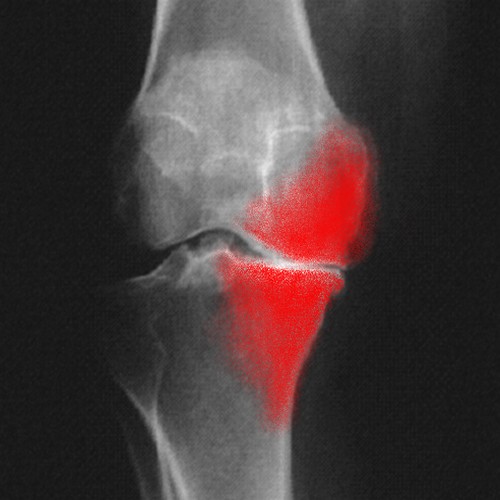

Arthrose genou : Articulation arthrosique

Lorsque l'articulation est le siège de l'arthrose, on observe :

. Un amincissement du cartilage ;

. Une densification de l'os adjacent ;

. Une déformation de l'articulation ;

. Une usure de l'os créant des petites cavités appelées « géodes d'hyperpression »;

. La présence d'excroissances osseuses dites « becs de perroquets ».

Ces manifestations sont facilement visibles sur les radiographies.